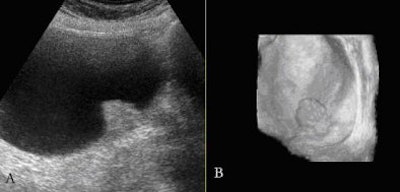

Small polypoidal lesions in the urinary bladder in the setting of relevant clinical symptoms can be malignant. Three-dimensional ultrasound helps render these small tumors, especially transitional cell carcinoma (TCC) in the urinary bladder, and delineates the surface characteristics in a much better way.

![]() |

| Small transitional cell carcinoma seen on 2D image (A), and rendered with irregular surface characteristics on the 3D sonocystoscopic image (B). |